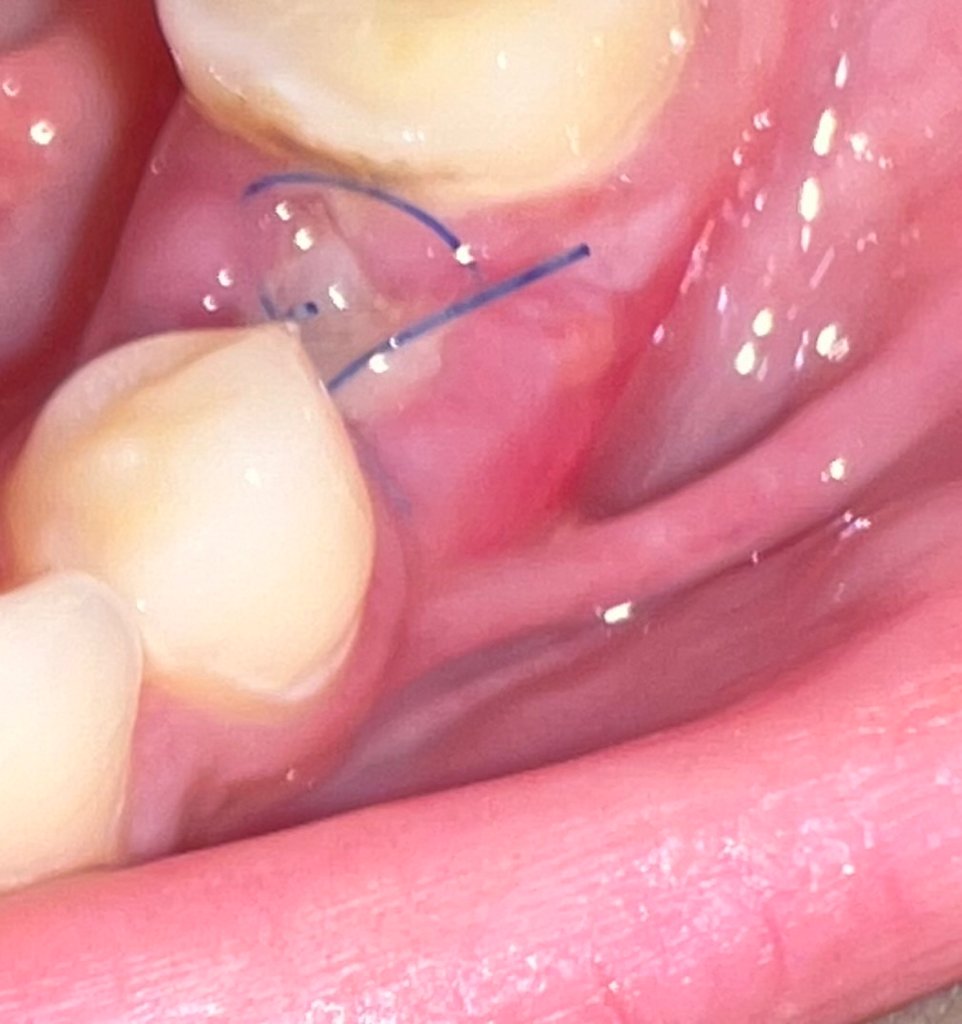

임플란트 뼈이식 후 6일차인데 염증인가요?

발치 후 바로 뼈이식 후 봉합을 했습니다.

1-2일차에는 안아프다가 4일차부터 아주 미세한 통증이 느껴지고 잇몸 옆에 뾰루지 같은 것이 났습니다. 그리고 다른 잇몸에 비해 좀 하얀 것 같습니다.

• 1번 째 사진